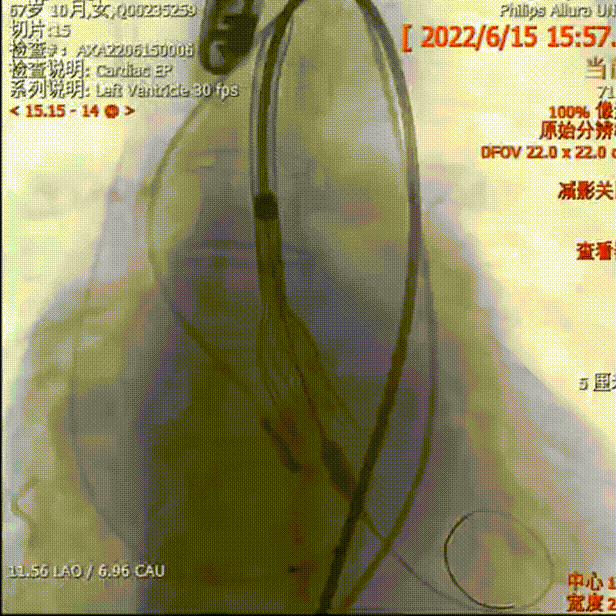

释放下滑回收

位置偏高回收

轻微瓣周漏